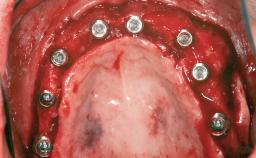

An 18-year-old man was referred for implant therapy in the posterior mandible to the Department of Oral Surgery and Stomatology (University of Bern, Switzerland). He was healthy and did not smoke. Tooth 35 was congenitally missing, involving a single-tooth edentulous space that offered an adequate mesiodistal dimension for implant placement but exhibited a typical pattern of buccal flattening. A panoramic radiograph was obtained, which revealed a sufficient vertical bone height above the mandibular canal and a normal bone structure in the edentulous area.

Bone Augmentation Horizontal|Staged

Augmentation Materials Autogenous chips|Autogenous block(s)|Xenogenous|Membrane